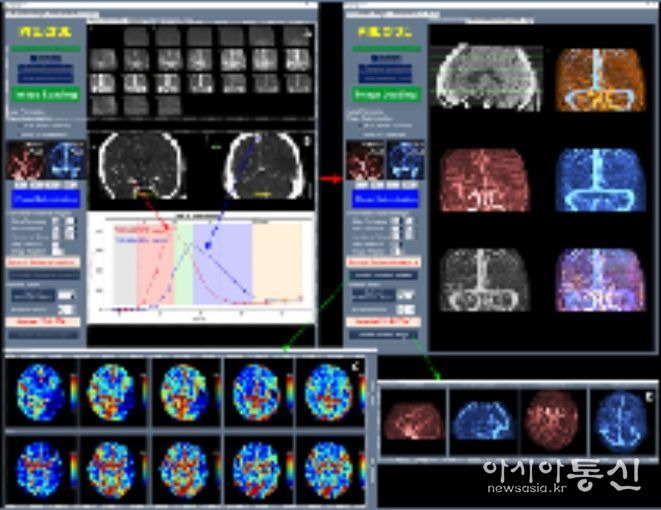

이와 함께 허혈성 뇌혈관 질환 환자를 대상으로 혈관재개통 치료가 필요한 환자 선별을 지원하는 소프트웨어 등 다양한 진단·치료 보조 AI 의료기기들이 혁신의료기기로 지정됐다.